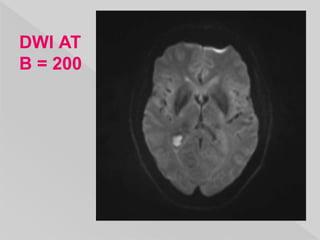

 three sets of images :

 isotropic diffusion map - DWI,

 the pulse sequence - ADC &

 B=0 images.

 an isotropic T2 weighted map as it represents

the combination of actual diffusion values and

T2 signal.

 It is a relatively low resolution image with the

following appearance:

 grey matter: intermediate signal intensity (grey)

 white matter: slightly hypointense compared to

grey matter

 CSF: low signal (black)

 fat: little signal due to paucity of water

 other soft tissues: intermediate signal intensity

(grey)

DWI AT

B = 200

 Acute pathology (ischemic stroke, cellular

tumor, pus) : increased signal denoting

restricted diffusion.

 b value measures the degree of diffusion

weighting applied,

 a larger b value is achieved by increasing the

gradient amplitude and duration and by

widening the interval between paired gradient

pulses.

 To sense slow moving water molecules and

smaller diffusion distances, b values should be

higher (e.g. b = 500 s/mm2).

 Apparent diffusion coefficient is calculated using

different b-values (e.g 0-1000 s/mm2).

 A useful rule of thumb is to choose the b value

such that (b X ADC) is nearly equal to 1.